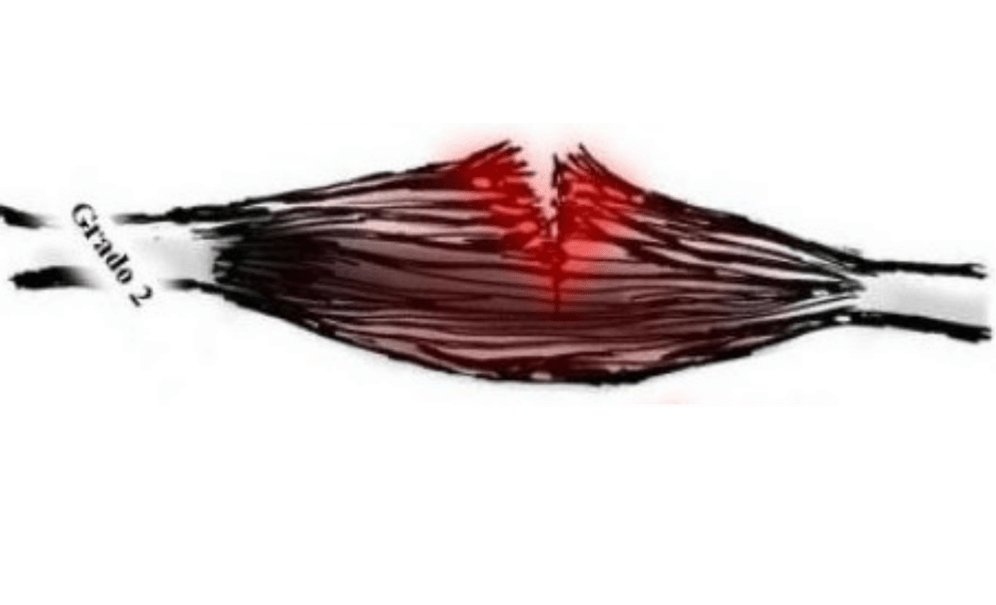

Grado II:

El compromiso en las fibras musculares es evidente e importante.

- Una ruptura parcial con dolor intenso que puede llegar a comprometer el movimiento y las actividades de la vida diaria.

- Inflamación considerable

- Enrojecimiento importante.

- Aumento de temperatura

- Puede aparecer hematoma (moretón) desde la lesión a la periferia al dia siguiente

Dependiendo del tamaño de la lesión y sus características, se realiza un abordaje invasivo o no invasivo (Cirugía o no cirugía)

Pronóstico de recuperación:

Variado dependiendo de la lesión, recuperación de las capacidades en un 80 a 85% en el tercer mes.